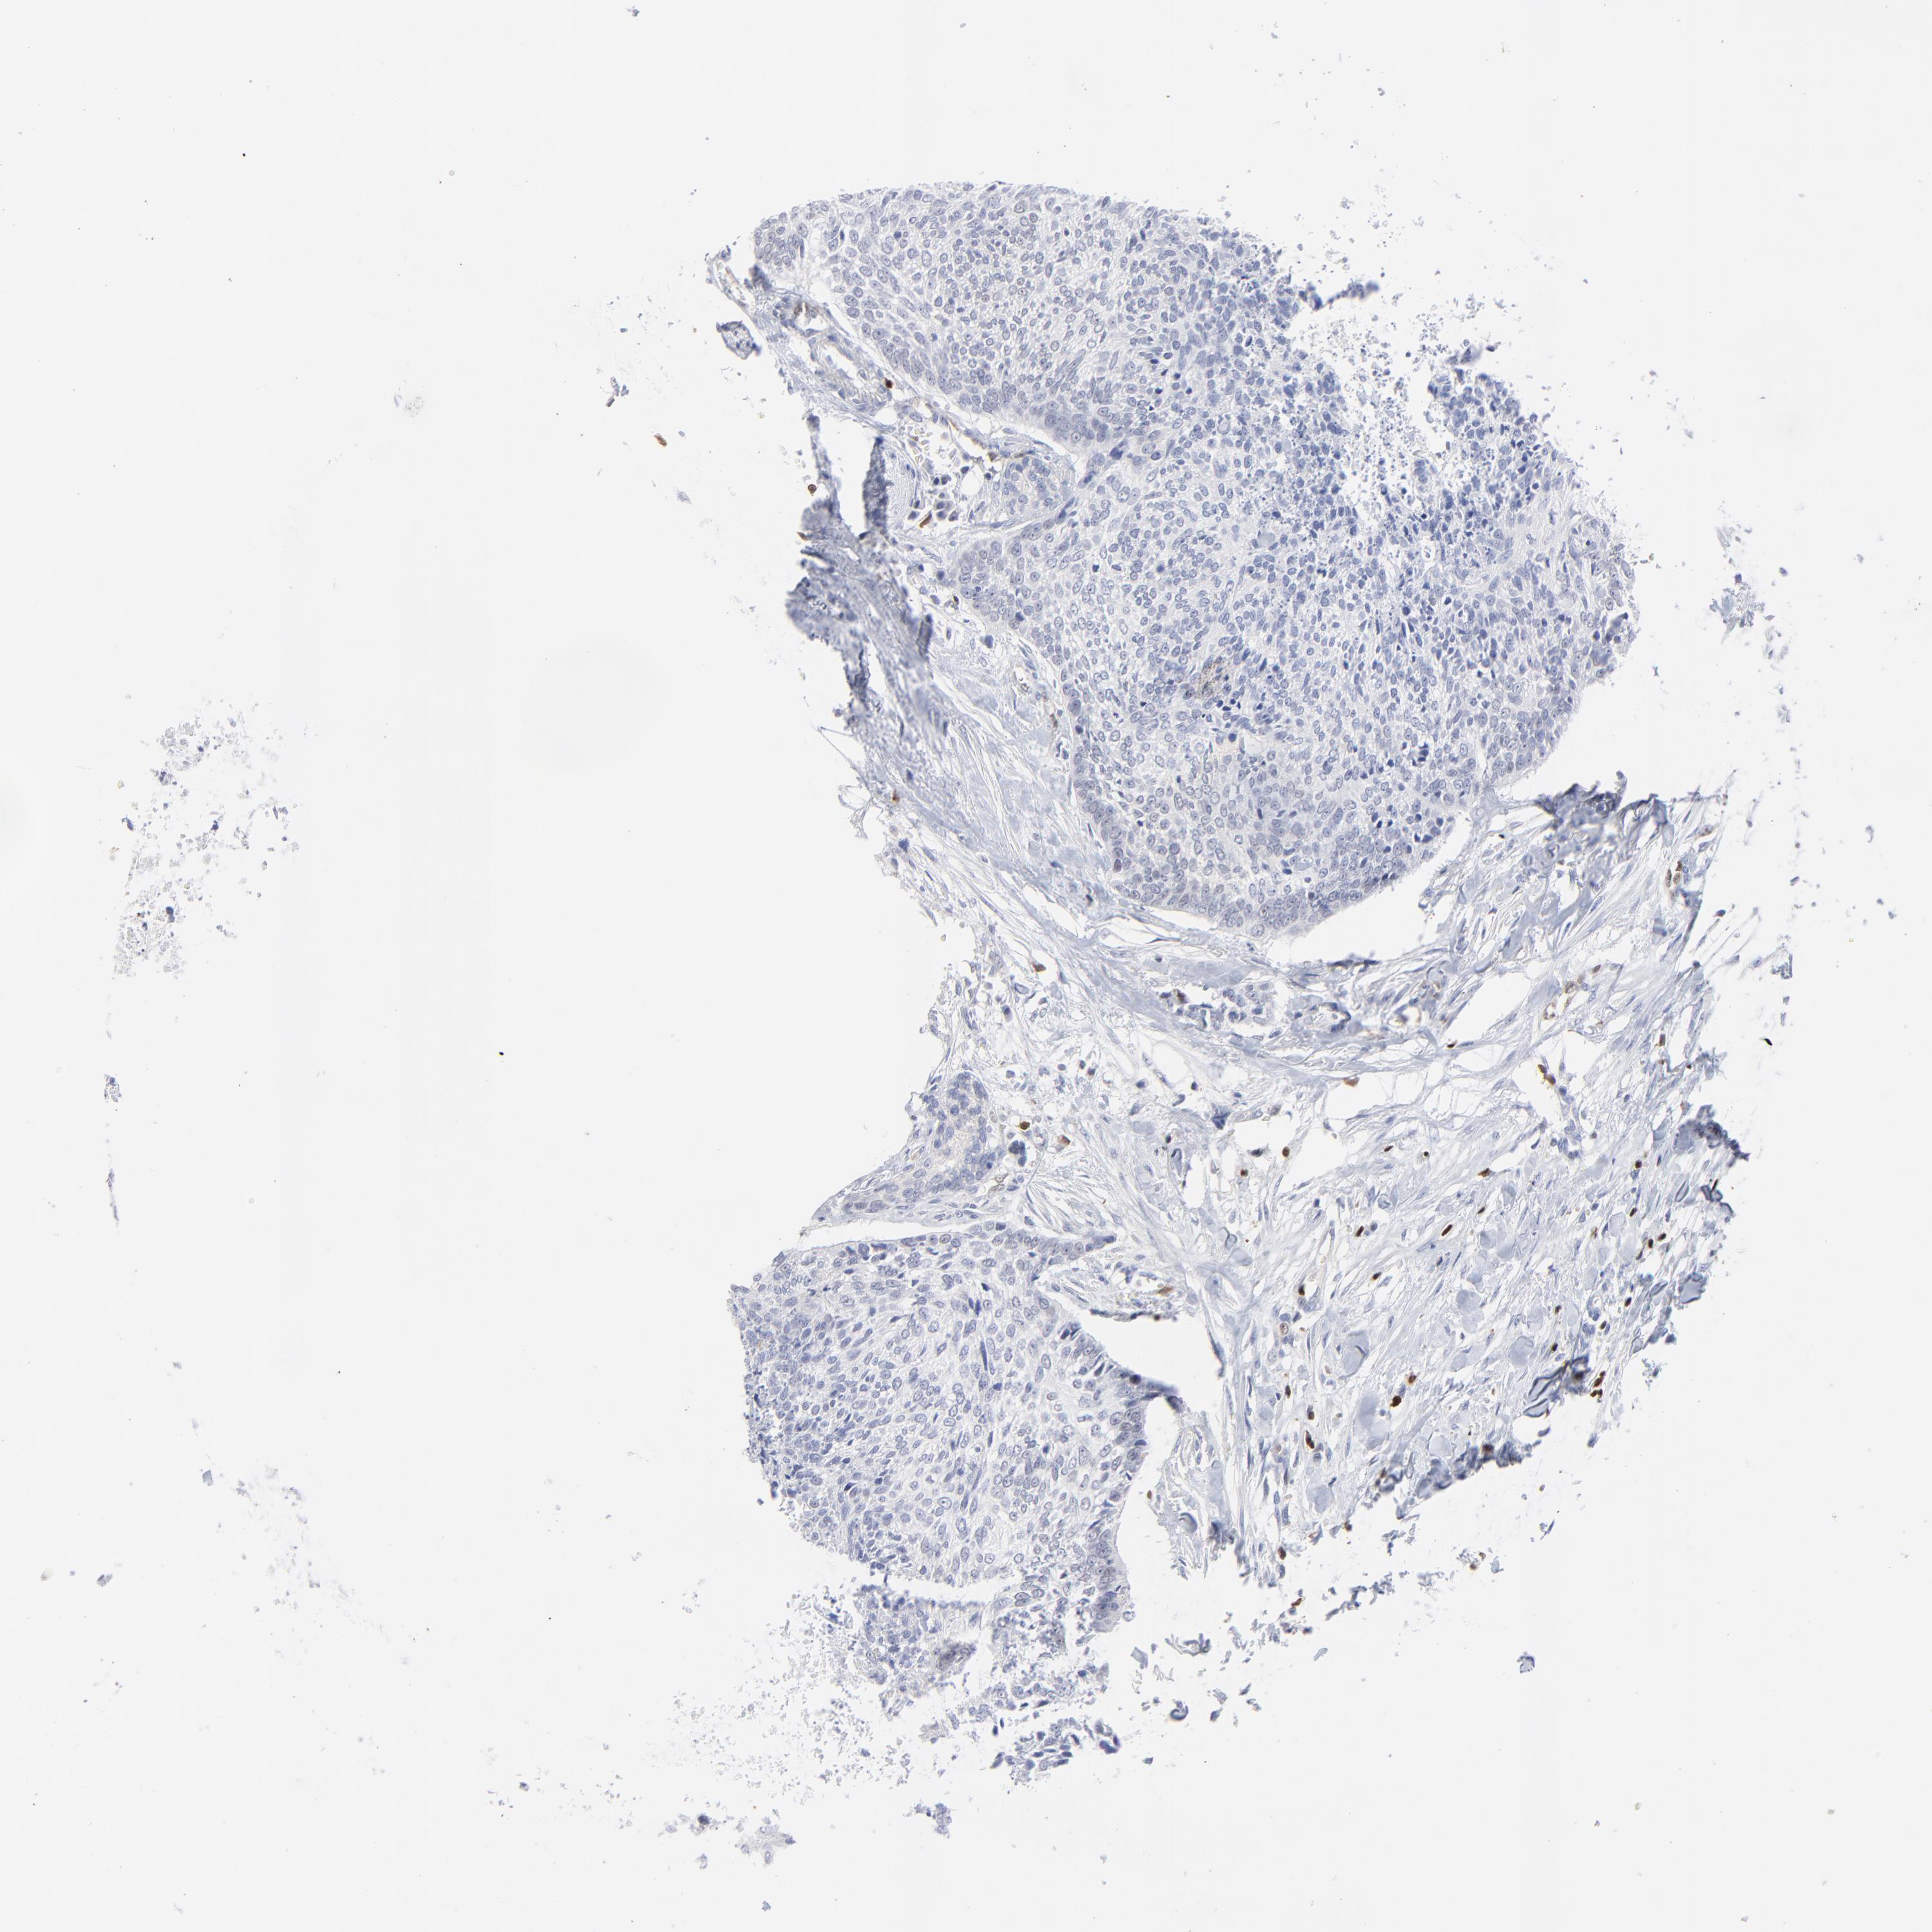

HEAD AND NECK CANCER - Protein expressioni

A mouse-over function shows sample information and annotation data. Click on an image to view it in a full screen mode. Samples can be filtered based on level of antibody staining by selecting one or several of the following categories: high, medium, low and not detected. The assay and annotation is described here.

Antibody stainingi

Antibody staining in the annotated cell types in the current human tissue is reported as not detected, low, medium, or high, based on conventional immunohistochemistry profiling in selected tissues. This score is based on the combination of the staining intensity and fraction of stained cells.

Each image is clickable and will lead to virtual microscopy that enables deeper exploration of all samples and also displays staining intensity scores, fraction scores and subcellular localization as well as patient and tissue information for each sample.

Antibody HPA003134

Antibody CAB002625

Staining

High

Medium

Low

Not detected

Intensity

Strong

Moderate

Weak

Negative

Quantity

>75%

75%-25%

<25%

None

Location

Nuclear

Cytoplasmic/membranous

Cytoplasmic/membranous,nuclear

Squamous cell carcinoma, NOS

Squamous cell carcinoma, metastatic, NOS